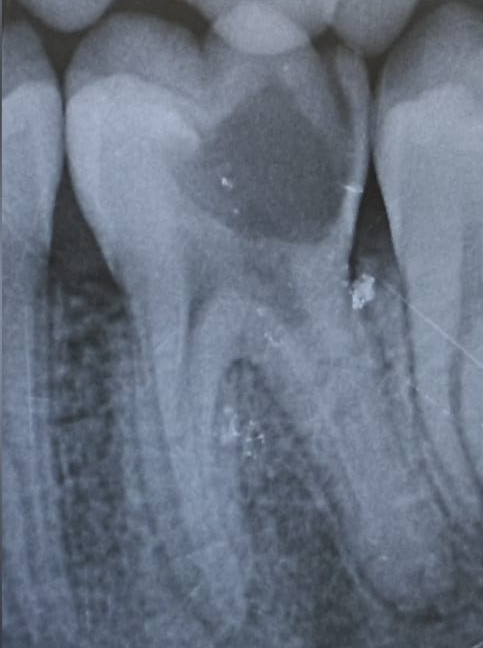

Caso Clinico

Restauri in composito

Il restauro di un dente cariato o fratturato si ottiene con il composito. È un materiale, in uso

da circa 45 anni, che diviene tutt’uno col dente.

È innocuo al dente e all’organismo. La gran parte dei restauri ha già superato i 35 anni.

Prima

Dopo